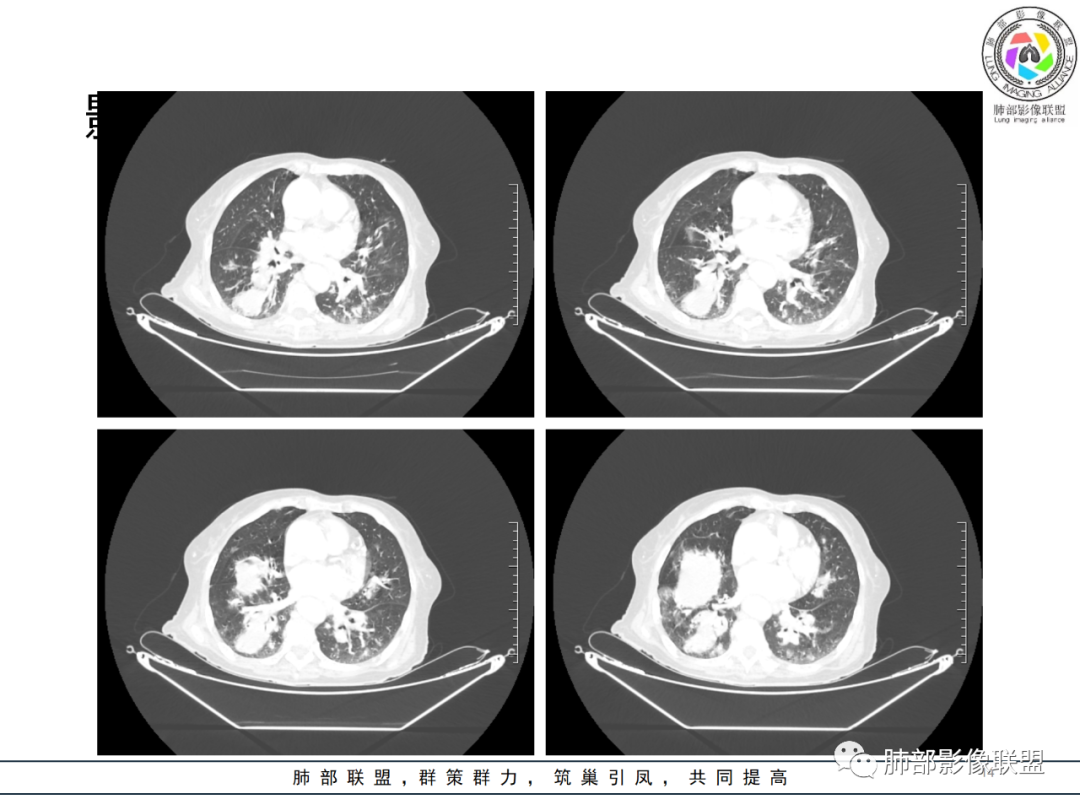

影像资料

老年女性,发热起病,两肺散在斑片状影,三个月后两肺病灶进展,支气管血管束增厚,结合发热病史、实验室检查LCH增高,肾脏及腹膜后淋巴结肿大,结合以上综合考虑符合淋巴瘤表现。

老年女性 3个月前发热,双肺支气管血管束增粗改变。3个月后再次发热,影像见双肺广泛支气管血管束明显增粗,较前进展,并延续进入纵隔,另外增强见双肾周增多软组织密度,左肾明显且肾门处形成肿块样改变。综合考虑肿瘤性病变可能性大,1.小圆细胞肿瘤类病变,淋巴瘤?2 全身组织细胞类病变,如ECD,需要看看骨组织有无问题。3 左肾恶性肿瘤并淋巴道播散,如弥漫性尿路上皮癌。最后考虑 淋巴瘤>ECD>左肾恶性肿瘤并转移。

老年女性,发热,白细胞不高,CRP增高,LDH增高,糖尿病。两肺支气管血管束周围实变、GGO,支气管相对通畅,提示淋巴间质或血管来源。三个月明显进展伴双肾浸润性病变、腹膜后淋巴结肿大,轻-中等程度强化。考虑淋巴瘤,鉴别系统性疾病(IgD4、血管炎)。

老年女性,双肺支气管管壁增厚,沿血管束走形分布结节及斑片影,复查病灶增多增大,部分呈点晕征改变,腹部左肾盂软组织密度影,周边淋巴结增大。考虑肿瘤并肺内转移,淋巴瘤?鉴别真菌感染,曲霉菌?

女性,82岁,发热5天入院,双肺自肺门处血管束增粗,扭曲,三个月后多发结节及实变影,延支气管血管束分布,部分支气管近端堵塞,左肾异常占位?伴有双侧肾上腺增粗,实验室血象略高,考虑IgG4?结节病?淋巴瘤?进一步穿刺活检。

82岁女性,反复发热入院,查外周血白细胞升高,抗生素治疗可缓解,支持细菌感染性发热,结合肾脏肿瘤,考虑泌尿系感染发热;CT提示双肺多发毛玻璃影,右下肺多发大结节影,3月复查,双上肺毛玻璃影/混合毛玻璃影增多,部分呈点晕征,右下肺多发肿块,可见支气管穿行,双下肺中轴间质增厚,左肾占位,肺部病变考虑:1.淋巴瘤 2.肾癌肺转移

老年女性,近期反复的发热,胸部CT基础尚可,心影增大,双肺下叶血管束增粗,3个月后复查 提示双肺多发磨玻璃密度影,并有磨玻璃影内部血管的穿行,双肺下叶血管束的增粗,纵隔窗下未见纵隔肿大的淋巴结,血管通畅,未见血管壁的增厚,左肾肿瘤?肺内病变不符合支气管束分布,暂不考虑吸入性,考虑淋巴管或血管源性病变。总体考虑非感染性病变可能性大,血管炎?淋巴瘤?

老年女性患者,发热就医,两肺片状影,沿支气管血管束分布,炎性指标升高,糖尿病基础,首诊考虑肺部感染合乎情理,这也是常见病!事实上,患者抗感染治疗好转出院。

三月后患者再次因发热就医,病灶在“原址”基础之上范围扩大,病灶增多(而非此起彼伏),就有些不同寻常,仅如此高龄,如此大范围感染,持续三月之久?太难以想象。